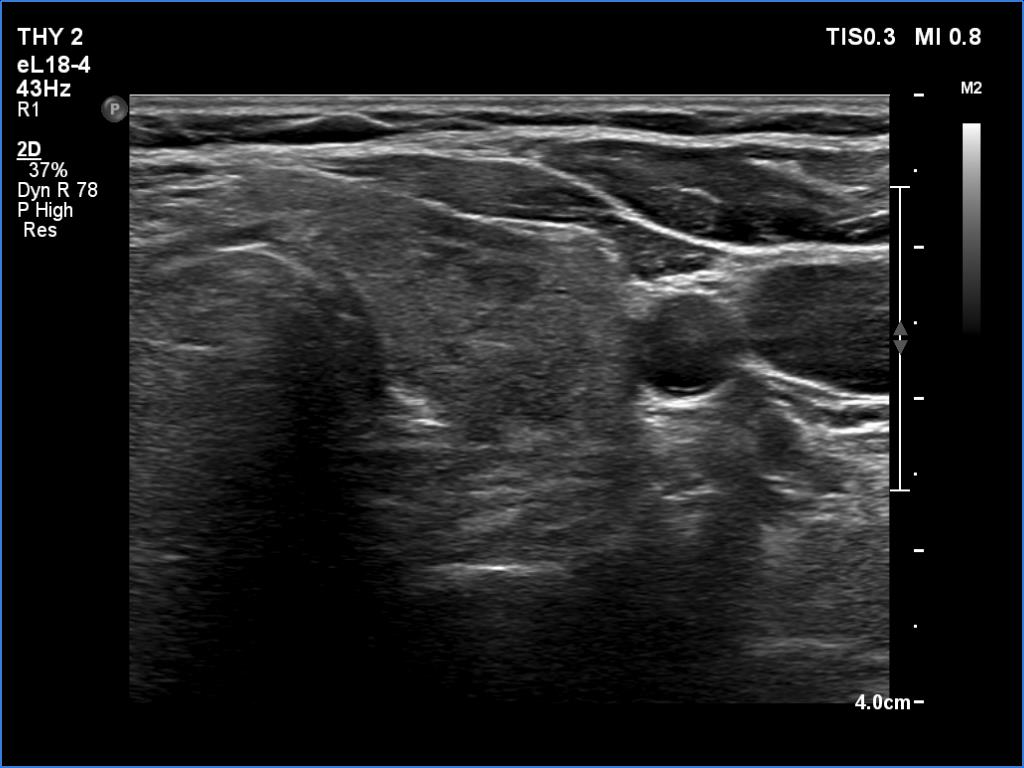

Lymphocytic thyroiditis - case 1441

Right lobe

Left lobe

Focal form of lymphocytic thyroiditis is presented. The thyroid has numerous discrete, hypoechoic lesions which correspond to more active foci of thyroiditis. The interpretation of the relatively large ventral hypoechoic area in the left lobe (right upper image can cause problem), however, longitudinal scan decides the issue: this field cannot be a pathological nodule.